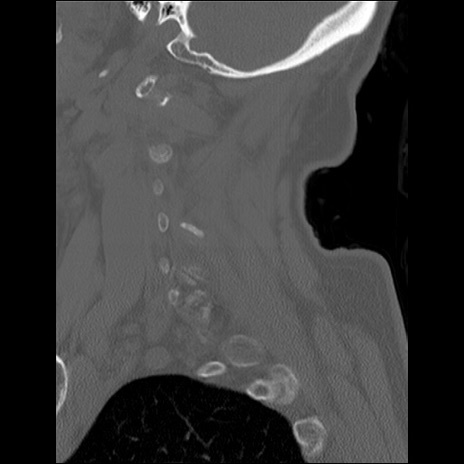

症例48 頚椎CT(矢状断像)

頚椎CT